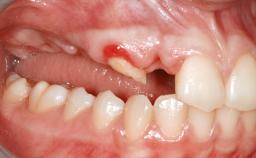

A 47-year-old Caucasian woman with a single-tooth edentulous space at the site of the left maxillary canine was referred for treatment. She had undergone traumatic extraction of this impacted canine several months before referral. Her chief complaint was the dissatisfying appearance of her smile. The patient desired a stable and esthetic rehabilitation of the site. Her dental history showed no evidence of periodontal disease or bruxism. She had no systemic diseases, was not taking any medications, and did not smoke. The extraoral examination revealed a high lip line and an inadequate soft-tissue volume at the defective canine site. Large black triangles were visible between the canine and its adjacent teeth.

Soft Tissue Anatomy Intact Defective

Bone Volume Horizontally and vertically sufficient Horizontally deficient Deficient vertically or deficient vertically AND horizontally